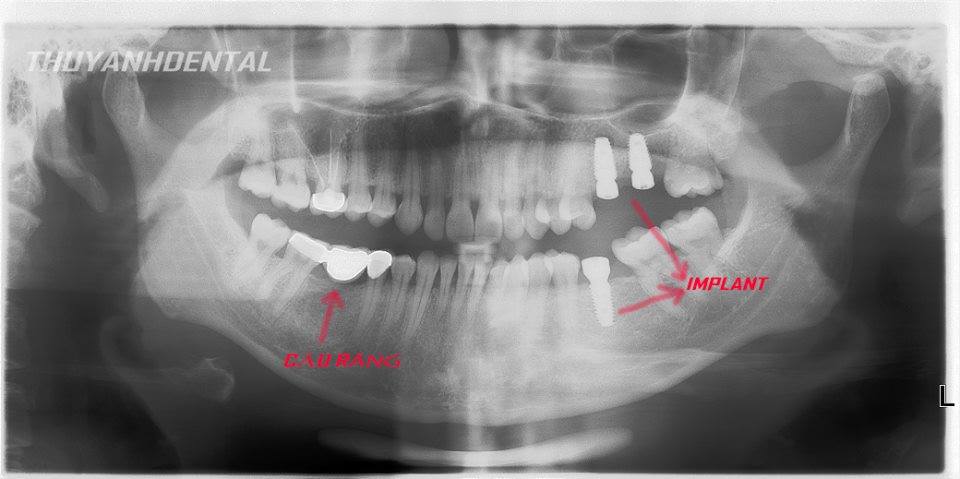

Phương pháp phục hình răng mất hiệu quả nhất tại Nha Khoa Thùy Anh Thái Nguyên

Về định nghĩa chúng ta có thể hình dung implant là 1 vít (chân răng nhân tạo) làm bằng chất liệu titanium (có tính tương hợp sinh học với cơ thể người) được cấy vào xương để thay thế chân răng mất, nhằm nâng đỡ phục hình răng sứ. Như vậy bản chất của quá trình thực hiện implant chính là cấy ghép trên cơ thể người, chính vì vậy để sử dụng được loại răng này cần có một thời gian nhất định cho vít implant ổn định trong xương hàm, thời gian trung bình cho quá trình là khoảng 3 tháng, tuy nhiên vấn đề còn phụ thuộc nhiều yếu tố chuyên môn khác nữa. Giải pháp implant hiện nay là tối ưu nhất cho các trường hợp thay thế răng bị mất vì độ bền cao, sức nhai mạnh, không phải mài các răng bên cạnh như làm cầu răng sứ

NHỮNG TRƯỜNG HỢP MẤT RĂNG NÀO CẦN CẤY GHÉP IMPLANT

- Khi bạn bị mất răng đơn lẻ

- Khi bị mất răng toàn bộ, có nhu cầu sử dụng hàm giả vững ổn, chắc chắn hơn

- Thay thế phục hồi hiện tại do đau, viêm, khó chịu

Khi có nhu cầu cấy ghép implant tại Thái Nguyên, Nha Khoa thùy Anh chính là sự lựa chọn hàng đầu